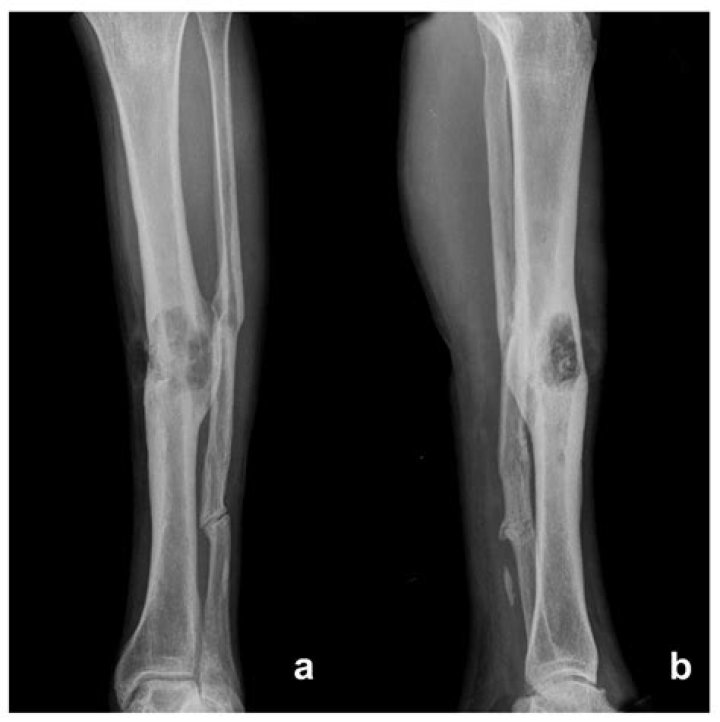

Can you replace tibia?

The tibia tumor is totally resected, and the tibia is replaced with a custom-made endoprosthesis. The endoprosthesis was enveloped in a Trevira tube to facilitate the attachment of soft tissues and the patella tendon.